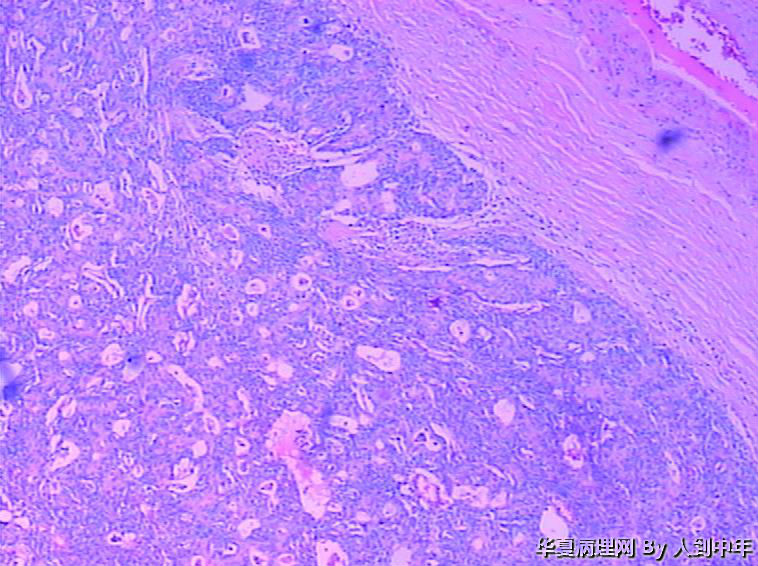

肺部肿瘤--类癌?求助大家

患者,男性,72岁,右肺中叶占位,肺门部肿物,散在多结节状,直径0.2-2.2cm。

• 肺部肿瘤--类癌?求助大家图2

图2

NT。需计数分裂像分级。

低分化癌,看到有腺样结构,肿瘤多结节,也要排除转移。

低分化癌,可能伴神经内分泌分化。不能标记也要建议会诊,去不去是他们的事

微囊、细胞梭形或立方、癌巢周边细胞见栅栏状(图22),不能排除基底细胞样癌。

癌,微囊、细胞梭形或立方、癌巢周边细胞见栅栏状,不能排除基底细胞样癌。多结节,也要排除转移性涎腺型恶性肿瘤,腺样囊腺癌等。